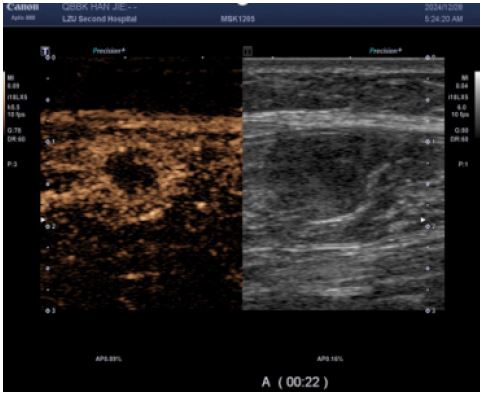

CEUS (performed next day): Demonstrated multiple hypoechoic foci in the left calf muscle layer. At 12 seconds post-contrast injection, lesions exhibited heterogeneous hyper-enhancement (> adjacent muscle tissue) with irregular non-enhancing areas.

Figure 3: CEUS suggested heterogeneous hyper-enhancement at 12 s of contrast injection.